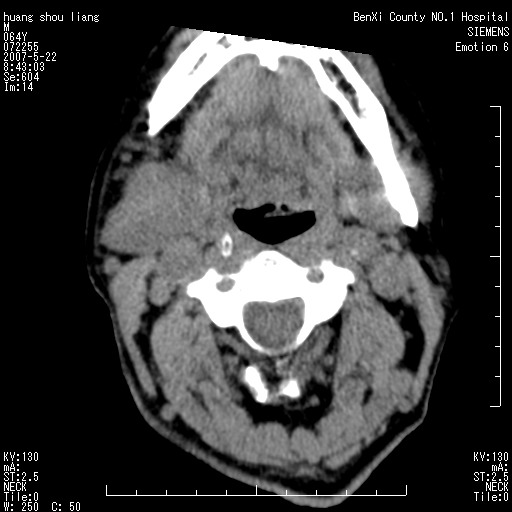

男性,64岁。颈部包块8年。最近增大。

对不起大家,可能是片子发太多有点乱,正常腮腺在下颌角的外侧,颌下腺在下颌体的中部内侧,本例在下颌角内侧偏下,和腺体一点关系都没有,从vrt和mpr上可以很明显看出来,再者肿块是好多粘连在一块的,大家在仔细看看,左侧可能也是吧,我还是考虑为肿大的淋巴结融合在一块,但性质??????

右侧腮腺下部均匀软组织密度肿块,外形不规则,与周围组织分界清晰,考虑右侧腮腺混合瘤或多形性腺瘤。

大家好,病理结果出来了,如大家所说,颌下腺混合瘤。

唉,解剖没学好吧,我诊断错了,不过还是有些不理解回去我在多看看书,谢谢大家的参与,以后我还会奉献好的病例。